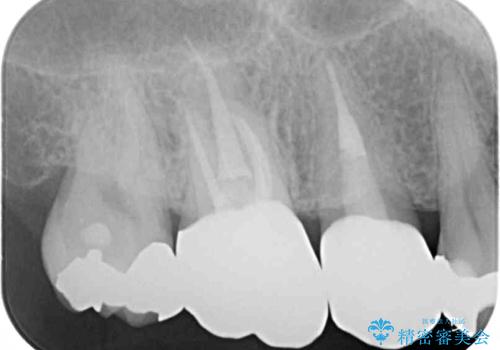

小臼歯は根管治療後に痛みが引きましたが、隣の大臼歯の痛みは引かなかったため、大臼歯も根管治療を行いました。

根管治療後に痛みは引き、半年後のレントゲン写真では根尖の病変の消失が認められました。